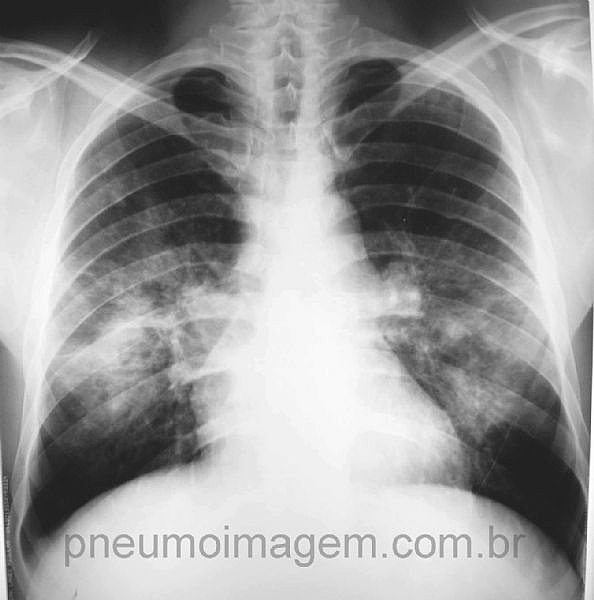

CASO CLÍNICO #24Essa imagem é característica de uma doença fúngica. Qual o nome desse sinal e a qual doença ele se relaciona?

This signal is characteristic of a fungal disease. What is the name of the sign and the disease which it relates?

Na radiografia observa-se o sinal da asa de borboleta. Este é sugestivo de paracoccidioidomicose.

Paracoccidioidomicose - sinal da asa de borboleta.

Sinal da asa de borboleta. Blastomicose sul americana.

Sinal da asa de borboleta/ paracoco.